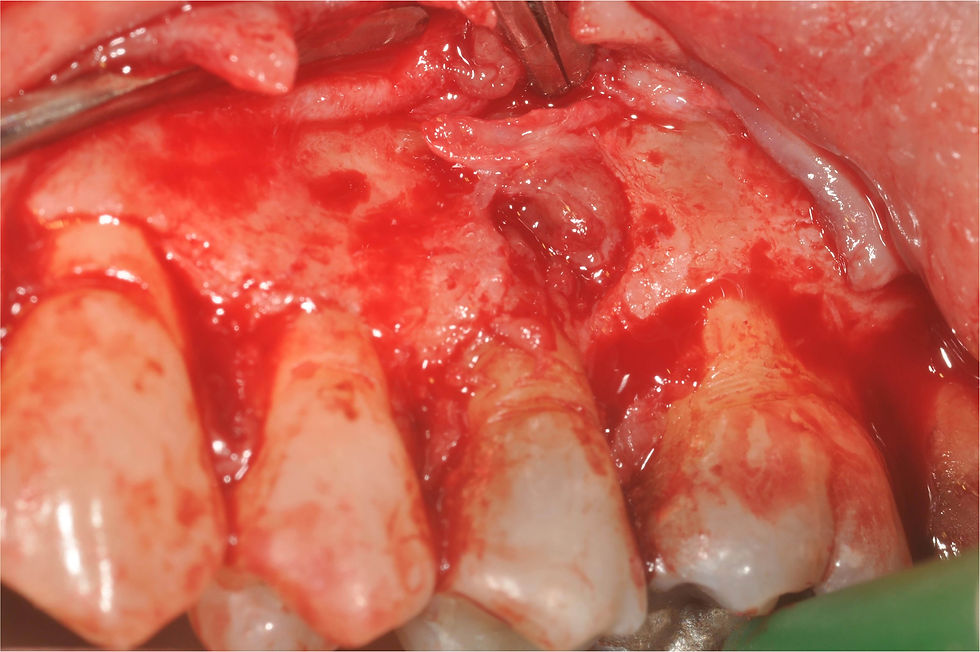

At the flap elevation, a very large lesion of the bone around the root’s fracture is evident.

Exposure of the lesion for its three-dimensional evaluation.